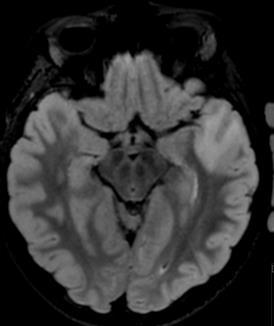

FIGUR 1: MR-bildene viser tydelig heterogenitet i hjernesvulster hos barn. A – Pilocytisk astrocytom i synsnerve (WHO grad ­1); B – Diffust astrocytom (WHO grad – 2); C – Høygradig gliom (WHO grad – 4); D – Diffust midtlinjegliom (WHO grad – 4); E ­ Dysembryoplastisk nevroepitelial tumor (WHO grad – 1); F – Gangliogliom (WHO grad – 1); G – Supratentorielt ependymom (WHO grad – 3); H – Pilocytisk astrocytom (WHO Grad – 1); I – Medulloblastom ( WHO grad – 4); J – Medulloblastom (WHO grad – 4); K – Ependymom ( WHO grad – 4); L ­ Glionevronaltumor forenlig med RGNT ( WHO – Grad 1). Alle pasienter har samtykket til bruk av bildene.